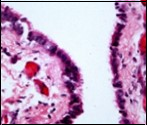

Alternatively, cutaneous ciliated cyst can be lined by non ciliated cuboidal or columnar epithelium with intermingled intercalated, dark or round peg cells. Foci of squamous metaplasia can be occasionally exemplified in the adherent epithelium whereas mucinous cells or apocrine-like features are exceptional 6, 8. Figure 1, Figure 2, Figure 3, Figure 4, Figure 5, Figure 6, Figure 7, Figure 8, Figure 9, Figure 10, Figure 11, Figure 12. 11, 12, 13, 14, 15, 16, 17, 18, 19.

Figure 4.Cutaneous ciliated cyst with a ciliated, pseudostratified columnar epithelium and vascularized fibrous tissue stroma (13).